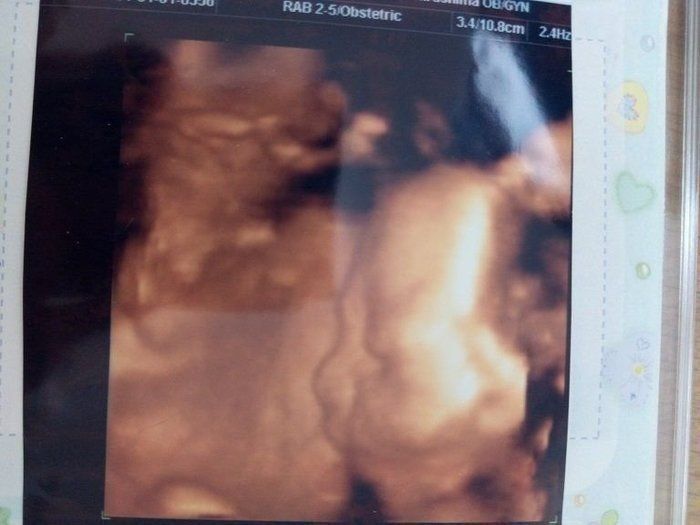

水野谷つむぎさんの妊娠26週目のエコー写真 4Dエコーに感動

初めて4Dのエコーで検査をしました。この日に性別を教えてもらえることになっていたので、とても楽しみに臨んだ検査では、股をしっかり開いて「男の子」を主張してくれました。右側に映るのが赤ちゃんの横顔です。顔がはっきりと見え、嬉しくて何度も見返していました。でも鼻が低いのが私に似ているようで、「可哀そうに」とも思っていました。